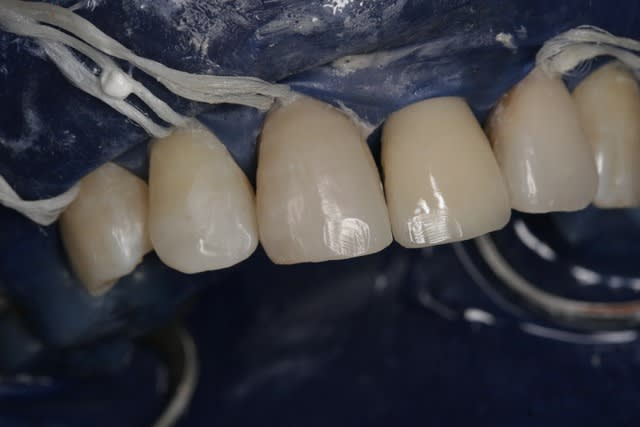

J'ai acheté le Aenial et essayé aujourd'hui sur 3 compos : 11D, 21M, 22M.

J'ai passé du temps même si j'ai pris plus que les SC.

Retour d'expérience avec du Gaenial après quelques cas. Ca tient bien la route, cependant il faut oublier le pinceau silicone qui étale mal ce produit. C'est moins évident de caractériser les bords libres, on obtient une sorte de flou de translucidité entre le transparent TE (opalescent?) et les teintes émail (le plus souvent JE), ce n'est pas aussi net et délimité que chez Micérium, mais l'effet caméléon est cependant plus présent avec le GC ce qui permet d'obtenir un bon résultat plus rapidement. Pour le cas présenté ça donne environ 1H30 pour 2 composites "spot" sur 13 (mésial) et 12 (disto-palatin), 1 composite de bonne taille sur 12 (mésio-vestibulaire), et 2 facettes composite directes sur 11 (vitale), et 22 (dévitalisée), y compris pose/dépose digue, retouche bord libre de la CCM (antédiluvienne), mise en forme et polissage à 90%

Puis 15 minutes de polissage/brillantage 1 semaine après.

Le résultat n'est pas aussi naturel qu'avec le Micérium, mais on est dans du bon niveau tout de même et je pense avoir économisé une bonne heure, avec un peu plus d'expérience et en se défaisant de certains "tics" lié à l'habitude du Enamel HFO, on devrait encore gagner un peu de temps......ça va faire plaisir à la cnsd et à la sécu ça!!!!